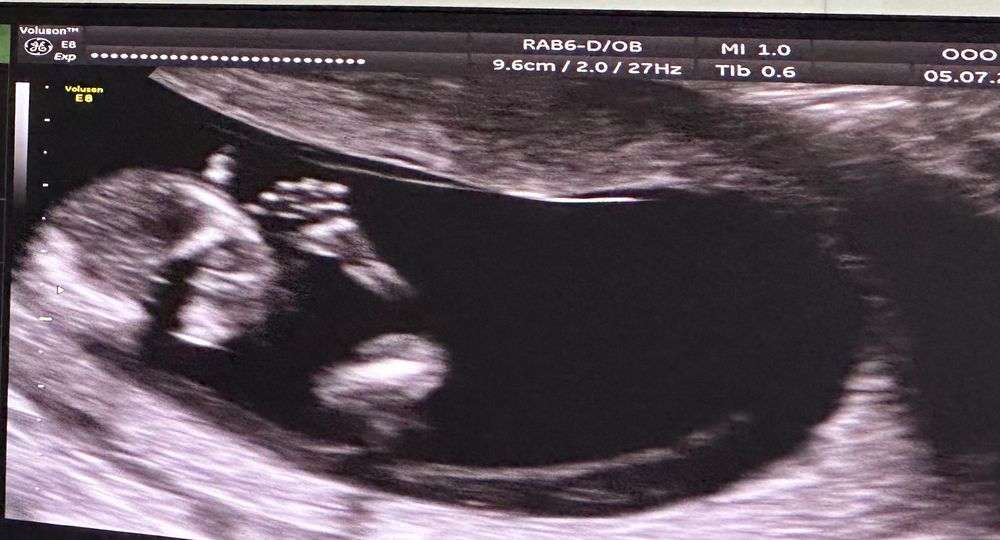

Оля в Благополучная беременность год 13/5 Нед узи УЗИ, КТГ, доплер Посмотрите еще 20 записей на эту тему Отменить Ответить Anastasiya Какой уже карапузик ❤️❤️❤️, как быстро летит время... 07.07.2024 Ответить Оля Anastasiya, по мне дык медленно :)))) но хотя бы 1 триместр пройден уже достижение 07.07.2024 Ответить Anastasiya Оля, впереди всё самое интересное😊😊😊 08.07.2024 Ответить Высокая чсс на 12 неделях, тахикардия плода Допплер фетальный Чаты Беременных Выберите чат: Январята-2026 Февралята-2026 Мартята-2026 Апрелята-2026 Майчата-2026 Июнята-2026 Июлята-2026 Августята-2026